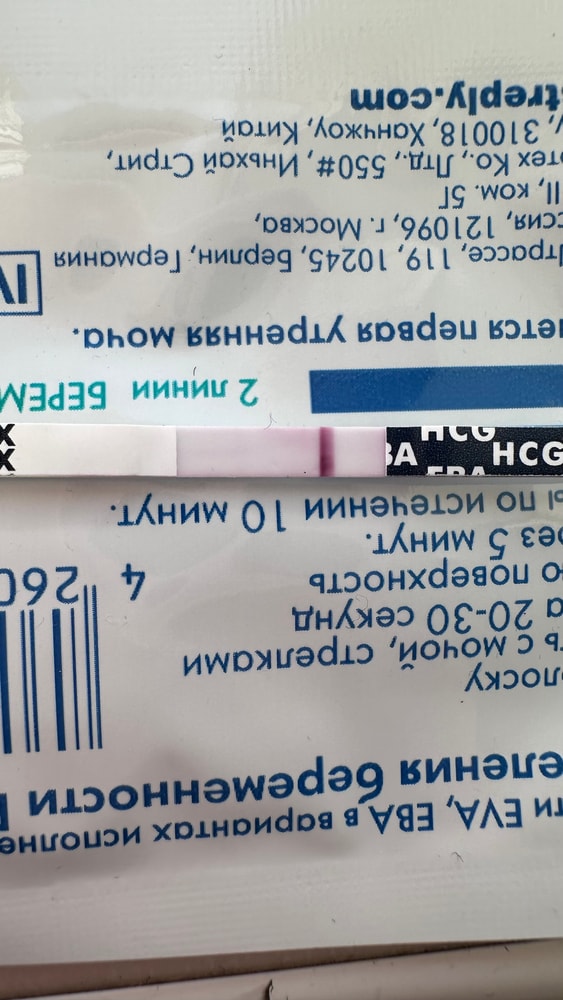

Писала сегодня пост с тенью на ЕВА

Писала сегодня пост с тенью на ЕВА

Вот и мне отреагентили эти прекрасные тесты.